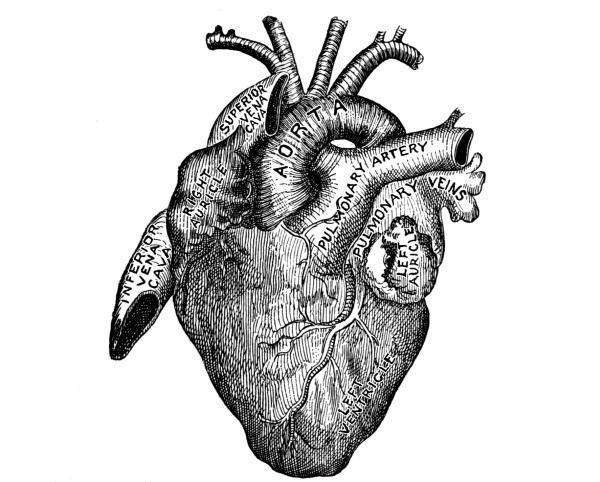

The Heart, 101—The Pericardium, 101—Cavities of the Heart, 103—The Endocardium, 103—The Valves of the Heart, 103—Circulation, 105—Circulation in the Fetus, 106—Arteries, 107—Veins, 109—Portal Circulation, 109—Pulmonary Circulation, 110—Nerves of the Heart, 110—Heart Sounds, 111—The Heart Beat, 111—Factors Affecting Circulation, 112—The Pulse, 113—Blood Pressure, 114—Nerve Supply of the Blood-vessels, 115—The Blood, 116—Composition of the Blood, 116—Coagulability of the Blood, 117—Blood-corpuscles, 118. |